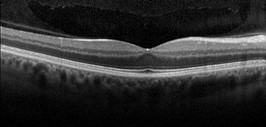

1. Оптична когерентна томографія (ОКТ)

Cучасний неінвазивний оптичний метод візуалізації, що використовується для отримання високороздільних шарових зображень сітківки ока.

Принцип роботи: прилад вимірює час затримки та інтенсивність відбитого світла, що дозволяє створити детальні тривимірні зображення шарів сітківки. Завдяки цьому можна оцінити їхню структуру, товщину, а також виявити патологічні зміни, такі як набряки, розриви чи відшарування.

Переваги застосування оптичної когерентної томографії (ОКТ):

Процедура проводиться швидко (до 2 хвилин), безконтактно та безболісно.

Метод дозволяє отримувати детальні тривимірні зображення сітківки та її шарів .

Ефективно діагностує захворювання на ранніх стадіях.

Використовується для діагностики широкого спектра захворювань (макулярна дегенерація, глаукома, діабетична ретинопатія тощо).

Немає впливу іонізуючого випромінювання або необхідності введення контрасту (крім флюоресцентної ангіографії за потреби).

Чітко візуалізує макулу, зоровий нерв та хоріоїдею.